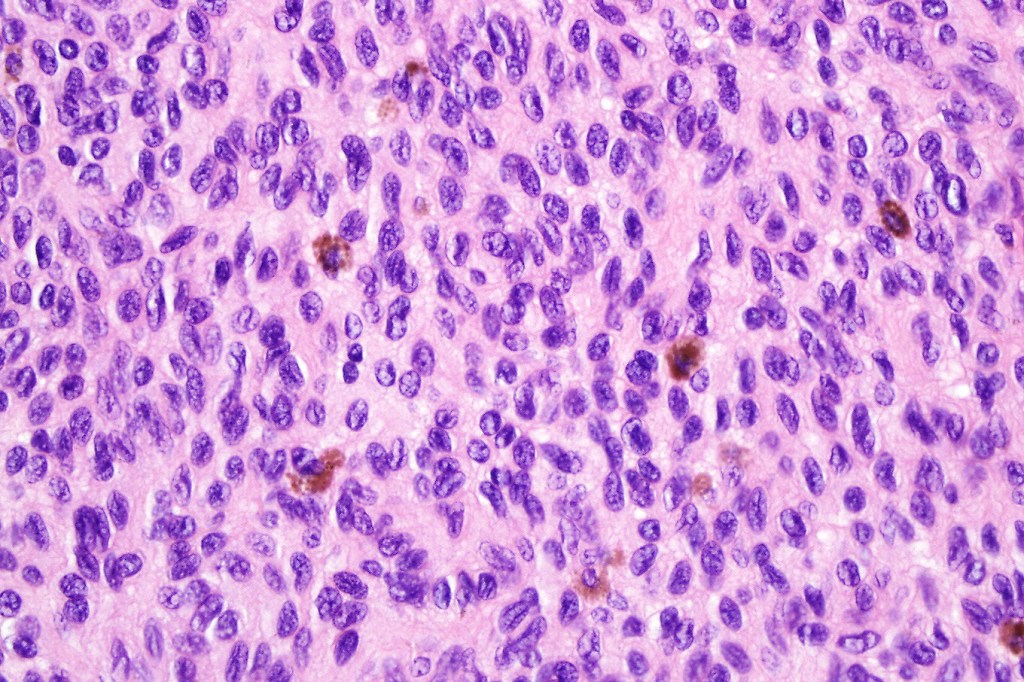

•It is hypercellular and most often composed of epithelioid cells showing little pleomorphism & only occasional mitoses

•Nuleoli are small

•Intracytoplasmic pseudo-inclusions

•The constituent cells are generally larger than the adjacent nevus cells

•Some examples show more marked pleomorphism with prominent nucleoli and increased mitotic activity but abnormal mitoses are not a feature. These are not associated with any sinister biological potential

•Spindle cell, small blue cell, blue nevus-like features, Spitzoid & proliferative nodules with mesenchymal differentiation (myofibroblastic, chondroid & osteoid) can be seen